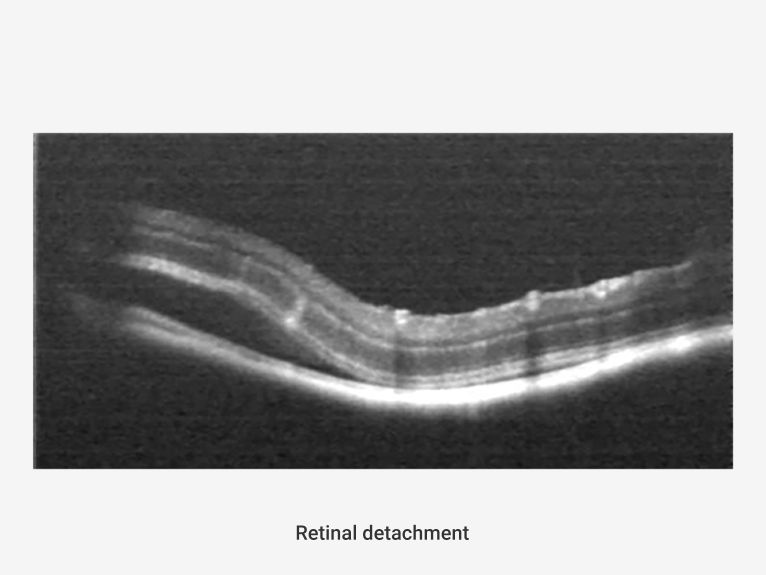

• Neurosensory Retinal Detachment